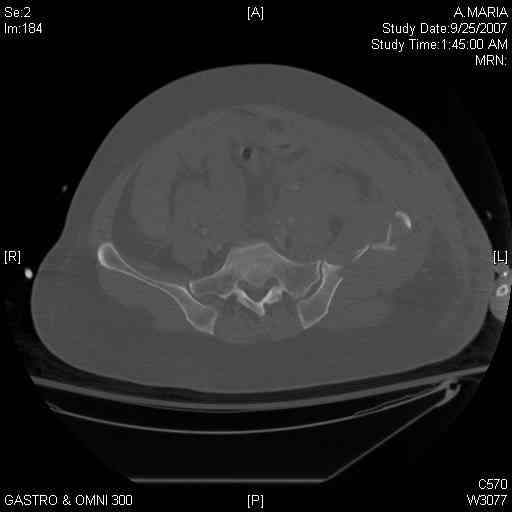

comminuted crescent fx

40 ish female ejected from car. Unstable, DPL negative, went to angio and had her pelvic bleeds embolized after many units of blood. GCS 6, floating elbow, clavicle, bothbones, etc.

My standard approach to this pelvis would be posterior, reduce/lag/plate thecrest, reduce/plate the caudal extent on the posterior crest and 1-2 lags back to front. In this case, the crest comminution seems to make plating all the way to the ASIS useless, as the plate would be on free floating fragments. Would plating the posterior extent of the fracture to secure the reduction at the SI joint and 2 screws back to front be sufficient fixation? Would anyone do a perc reduction and perc back to front screws, and would that be sufficient if the SI joint could be reduced (although I don't see how this could be accurately reduced closed). Would an ilioninguinal with a pelvic brim plate and posterior column screws be a better approach, although reducing the SI would be more indirect and less accurate?

It's a comminuted iliac fracture involving the GS notch and all that

implies...use the lateral interval of an ilioinguinal, sequentially reduce,

and fix...if you want to, you can attach the dominant unstable fragment to

both the stable posterior iliac fragment and also to the anterolateral portion of the sacrum using plates...if you choose to anchor to both, the implants get congested on the iliac side of the SI joint so be precise with contouring and such applications...perhaps and based on the images shown, an iliosacral screw would only augment the construct if applied to the second sacral segment (but this is difficult to assess on the images shown). The crest components can be held securely with screws and/or peripheral plating.

Thanks. I probably didn't include enough images on the CT, but it didn't look to me like an SI screw would be of value except into S2, which I am not

comfortable placing. I will post finals if the neurosurgeons let me operate on her. ICPs still a problem.

I always manage these percutaneously. The basic idea is to peg the AIIS fragment to the crescent frag still attached to the sacrum.

But the reported results of open treatment are very good, so your plan of ORIF should yield acceptable results.